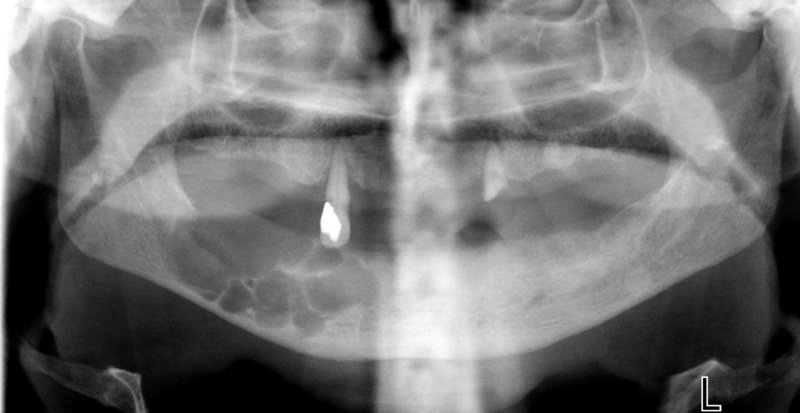

Οδοντογενής Κερατινοκύστη (πολύχωρη) .

- Οι μικρές βλάβεις είναι συνήθως μονόχωρες, ενώ οι μεγάλες βλάβες πολύχωρες με την ακτινογραφική εικόνα φυσσαλίδων από σαπούνι ή κερήθρας.

- Τα όρια της αλλοίωσης είναι σαφή, καλά καθορισμένα και ορισμένες φορές περιγράφονται ως ‘δαντελωτά’.